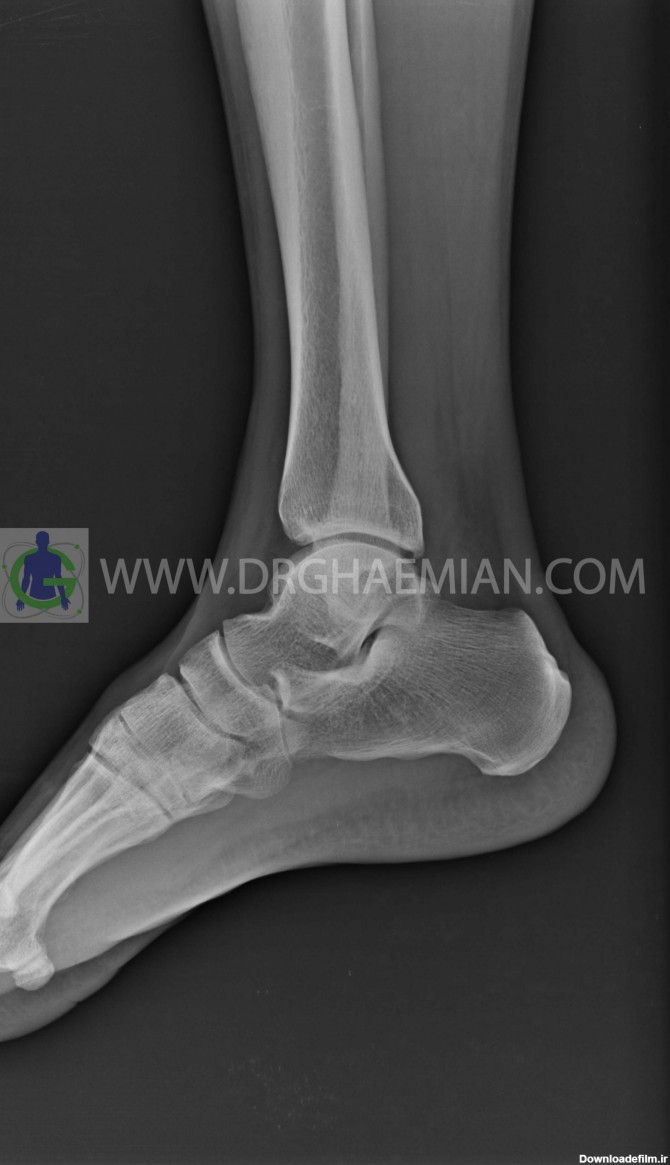

رادیولوژی مچ و کف پا در منزل تهران و کرج رادیولوژی در منزل مچ پا و کف پای انسان یک روش تصویربرداری پزشکی است که برای مشاهده و تحلیل ساختارهای داخلی مچ پا، از جمله استخوانها، مفاصل، و بافتهای نرم، به کار میرود. عکس مچ پای انسان به ویژه در تصویربرداری مچ پا، میتواند در تشخیص شکستگیها، آسیبها، التهابات، یا مشکلات مربوط به استخوانها و مفاصل کمک کند. رادیولوژی در منزل مچ پا و مچ دست در منزل تهران و کرج یک روش تصویربرداری پزشکی است که برای مشاهده و تحلیل ساختارهای داخلی مچ پا، از جمله استخوانها، مفاصل، و بافتهای نرم، به کار میرود. عکس مچ پای انسان به ویژه در تصویربرداری مچ پا، میتواند در تشخیص شکستگیها، آسیبها، التهابات، یا مشکلات مربوط به استخوانها و مفاصل کمک کند.

برای درمان شکستگی مچ پا ابتدا باید تشخیص به درستی صورت بگیرد. مهم ترین ابزار برای تشخیص این نوع شکستگی بررسی تصاویر رادیوگرافی است.